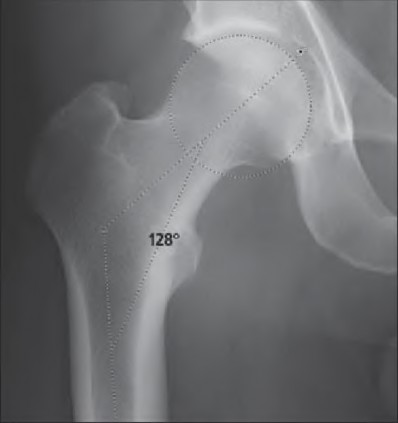

A 72-year-old female presents with progressive left thigh and knee pain for the last year. 5 years ago she sustained a femoral neck fracture treated with the implant seen in Figures A-C (current radiographs). The thigh pain is worse with weight-bearing. C-reactive

protein and erythrocyte sedimentation levels are within defined limits. Which of the following is the most likely cause of her pain?